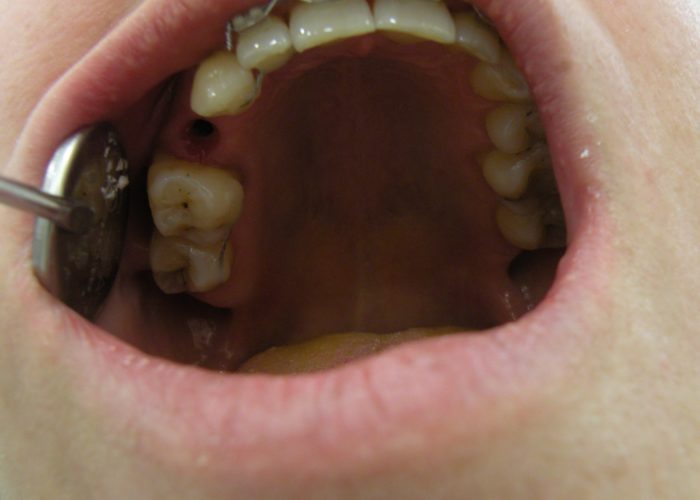

Interdisciplinarietà

Si tratta di una collaborazione interdisciplinare di un team di vari specialisti in odontoiatria, con un unico scopo: il raggiungimento di risultati perfetti nella riabilitazione della cavità orale di ogni singolo paziente.